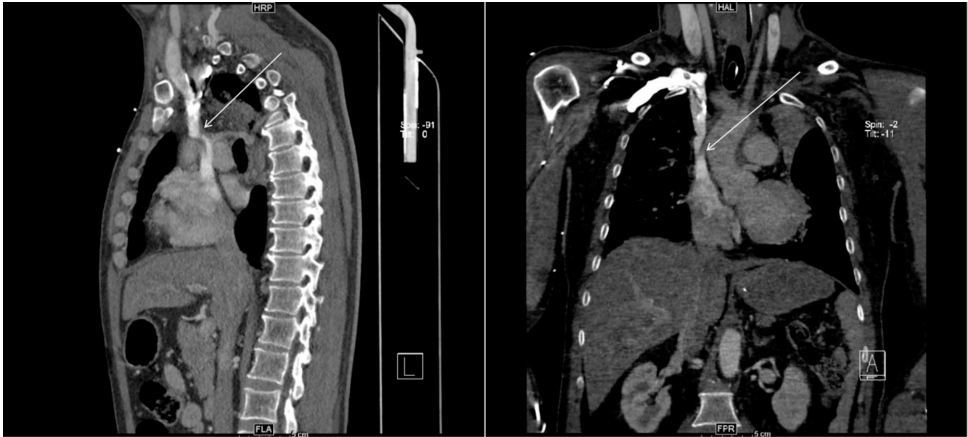

术前CT血管重建显示SVC入心处成角(图3)

ECMO期间增强CT证实导管尖端对应位置SVC狭窄(图2/4)

通过对比术前/术中CT,首次捕捉到ECMO导管加剧SVC成角至功能性狭窄的动态过程。三维曲面重建(CPR)技术直观显示导管与血管壁的机械性冲突。